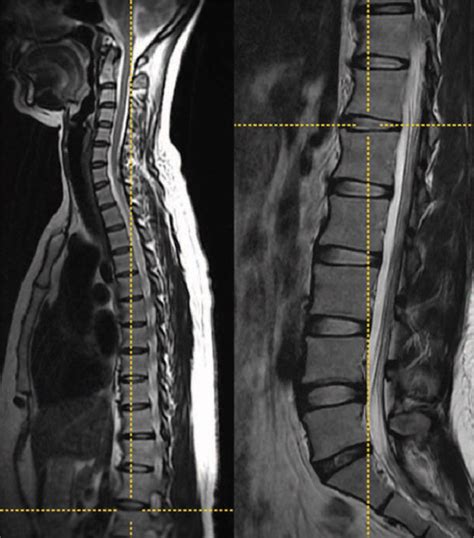

• MRI Scans: Provide information about the soft tissues and can help assess the impact of LSTV on the spinal cord and nerves.